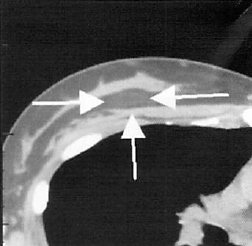

検査については、CT画像診断などを用いて精査を行います。

胸にしこりを見つけたとき、すぐに乳がんかもと考えてしまいがちですが、脂肪注入によるしこりの多くは良性と考えてよいでしょう。まずは、診断をしなければならないため、触診、CT検査などを行って、しこりの状態を正確に把握します。

画像診断を確認したら、摘出手術に取りかかります。手術は、なるべく乳房自体にキズアトを残さないように配慮し、皮膚を切る部分を決定します。